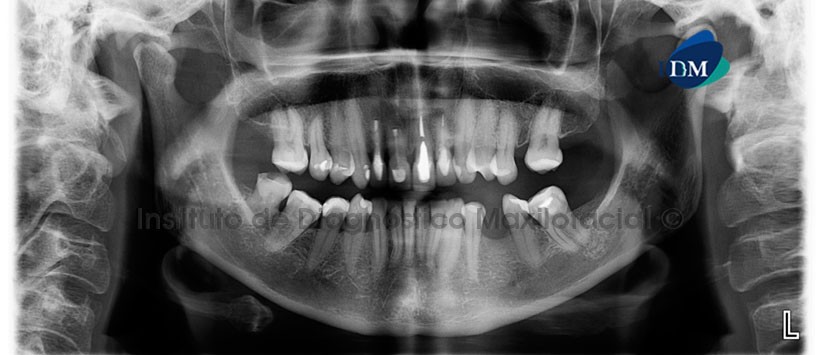

En la radiografía panorámica (Figura 1) se observa restauraciones protésicas coronarias, espigo y obturación de conductos, secuela de cirugía apical en piezas 12, 11, se aprecia además una banda radiolúcida en sentido cefálico-caudal a nivel de piezas 12 y 11.